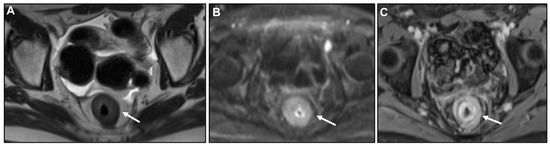

Malignant Target Sign

Homogeneous Delayed Enhancement

Concentric Ring Pattern

- Ha, H.K.; Jee, K.R.; Yu, E.; Yu, C.S.; Rha, S.E.; Lee, I.J.; Hee, J.Y.; Jin, C.K.; Kun, C.P.; Ho, Y. CT features of metastatic linitis plastica to the rectum in patients with peritoneal carcinomatosis. AJR Am. J. Roentgenol. 2000, 174, 463–466. [Google Scholar] [CrossRef]

- Burgain, C.; Germain, A.; Bastien, C.; Orry, X.; Choné, L.; Claudon, M.; Laurent, V. Computed tomography features of gastrointestinal linitis plastica: Spectrum of findings in early and delayed phase imaging. Abdom. Radiol. 2016, 41, 1370–1377. [Google Scholar] [CrossRef]